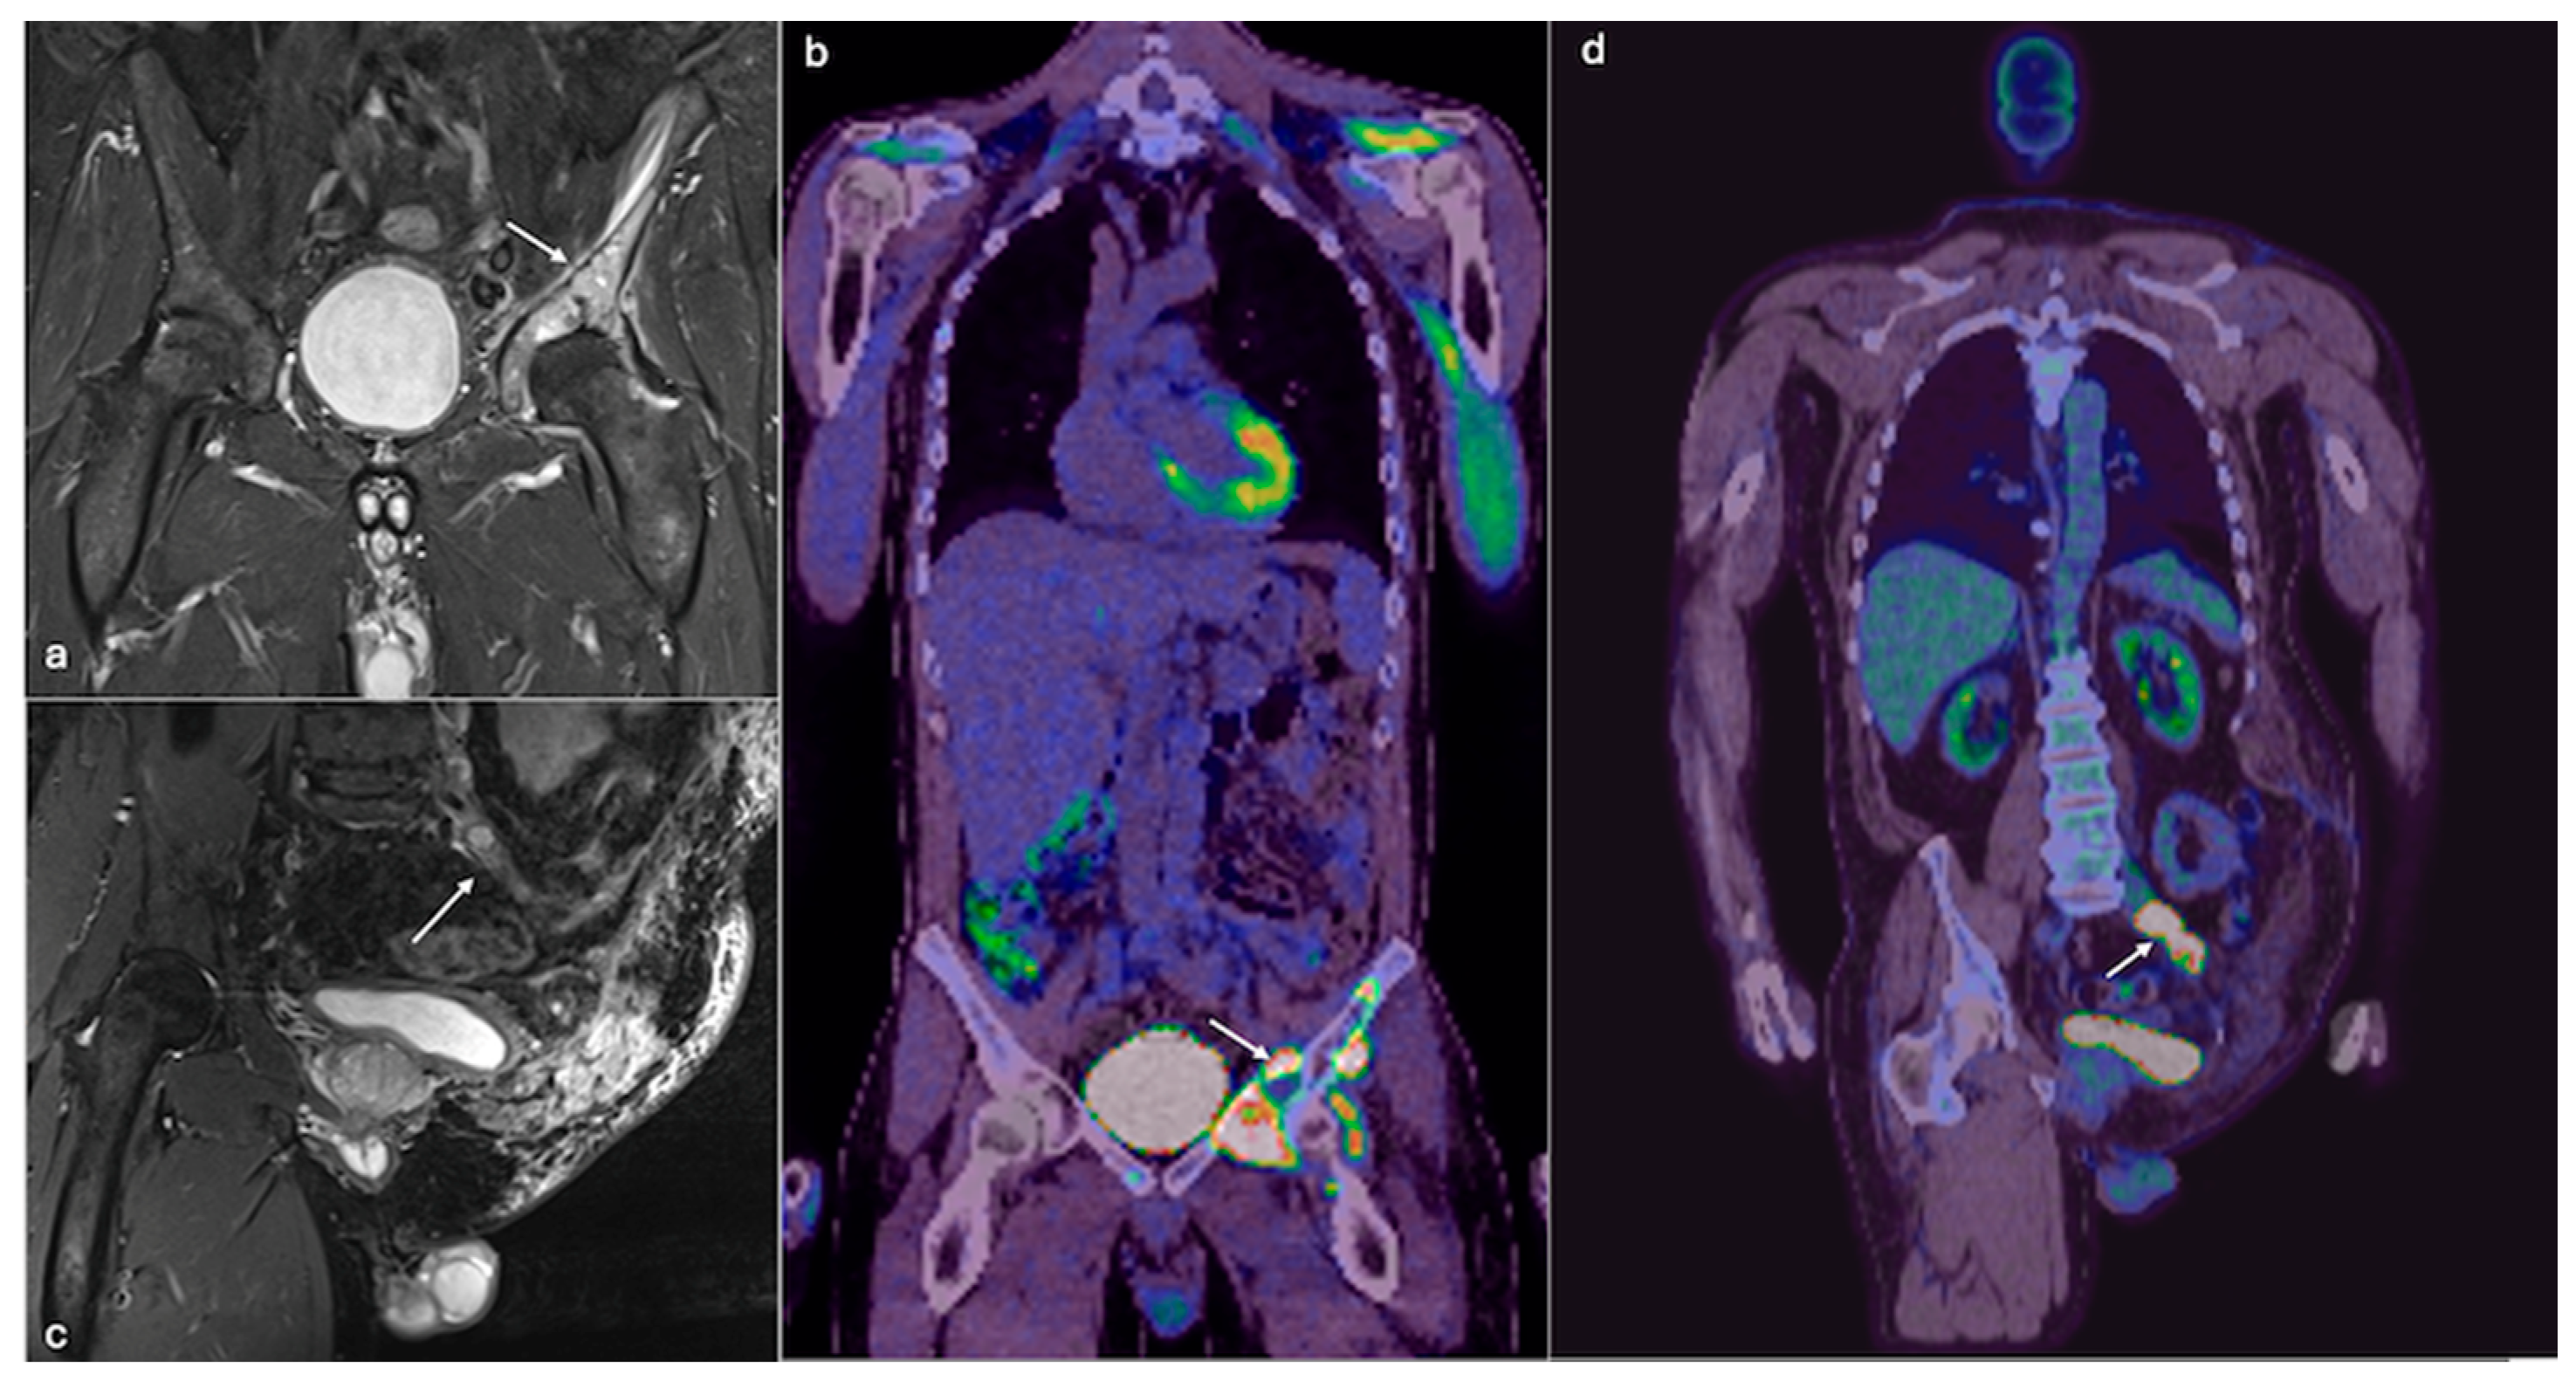

4.2. Chondrosarcoma